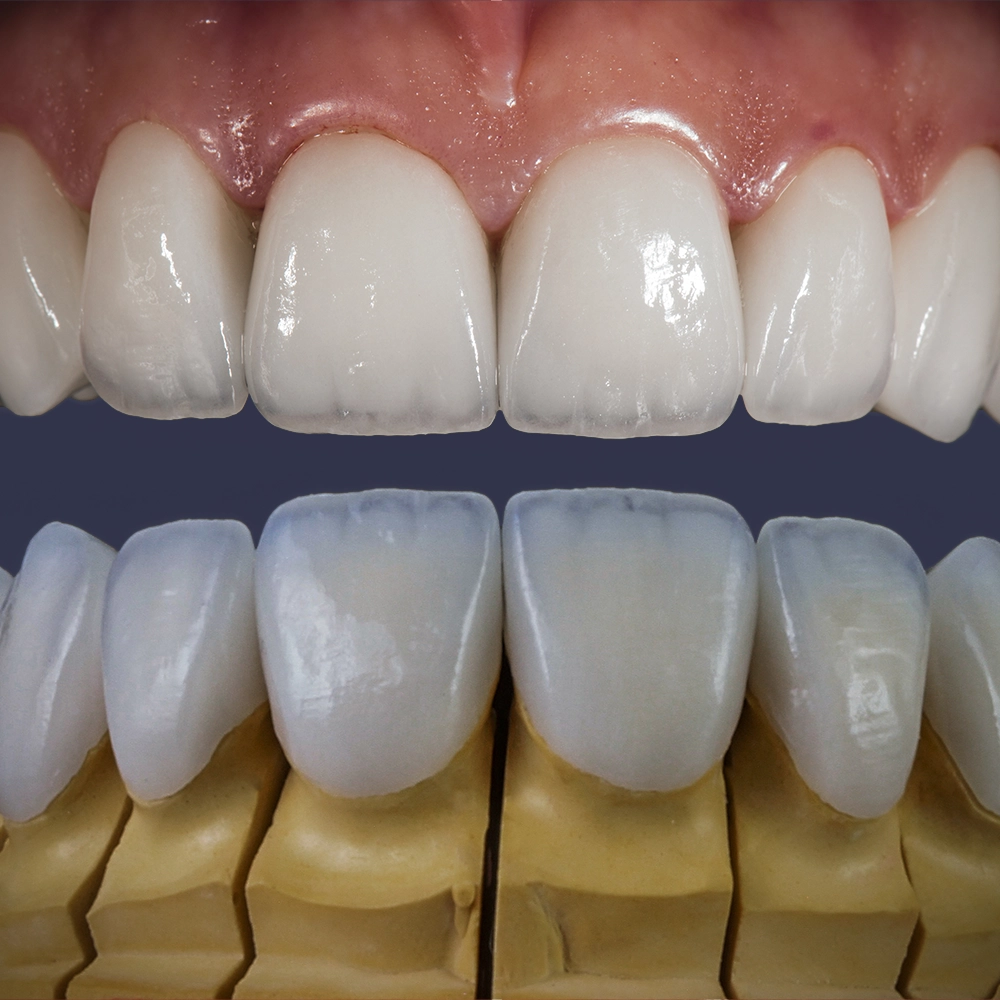

Ultra-thin veneers are a type of cosmetic dental restoration made from high-quality, durable materials that expertly mimic the translucency and texture of natural enamel. These advanced veneers offer a revolutionary solution compared to traditional veneers, which often necessitate significant removal of tooth enamel. Designed to be as thin as a contact lens, ultra-thin veneers require minimal tooth alteration, thereby preserving more of your natural tooth structure. This innovative approach not only maintains the health and integrity of your teeth but also ensures a stronger and longer-lasting result. By choosing ultra-thin veneers, you benefit from a minimally invasive treatment that enhances your smile while supporting your overall oral health.

Ultra-thin veneers are crafted from high-quality materials that closely resemble the look and feel of natural teeth. The translucency and texture of these veneers mimic the appearance of real enamel, ensuring that your smile looks natural and aesthetically pleasing. Each veneer is custom-made to match the color, shape, and size of your existing teeth, blending seamlessly with your natural smile. This attention to detail ensures that your veneers are virtually indistinguishable from your natural teeth, providing you with a flawless, beautiful smile.

The process of getting ultra-thin veneers typically involves several steps. First, during the initial consultation, we will discuss your goals and take impressions and photographs of your teeth. Next, we will minimally prepare your teeth generally less than 0.5mm of preparation (sometimes little or no preparation is needed depending on the design). Then you'll leave with a 'trial smile' and temporary veneers in place, after which we'll have a follow-up appointment the next day for final evaluation of your temporary veneers for tweaks and fitting to help guide the lab to your custom smile. Your veneers are finally crafted in a premier dental lab. Finally you'll return to the office where your custom, ultra-thin veneers are bonded to your teeth using biocompatible materials. The entire process usually takes one to four weeks from start to finish depending on the lab and complexity of the case.